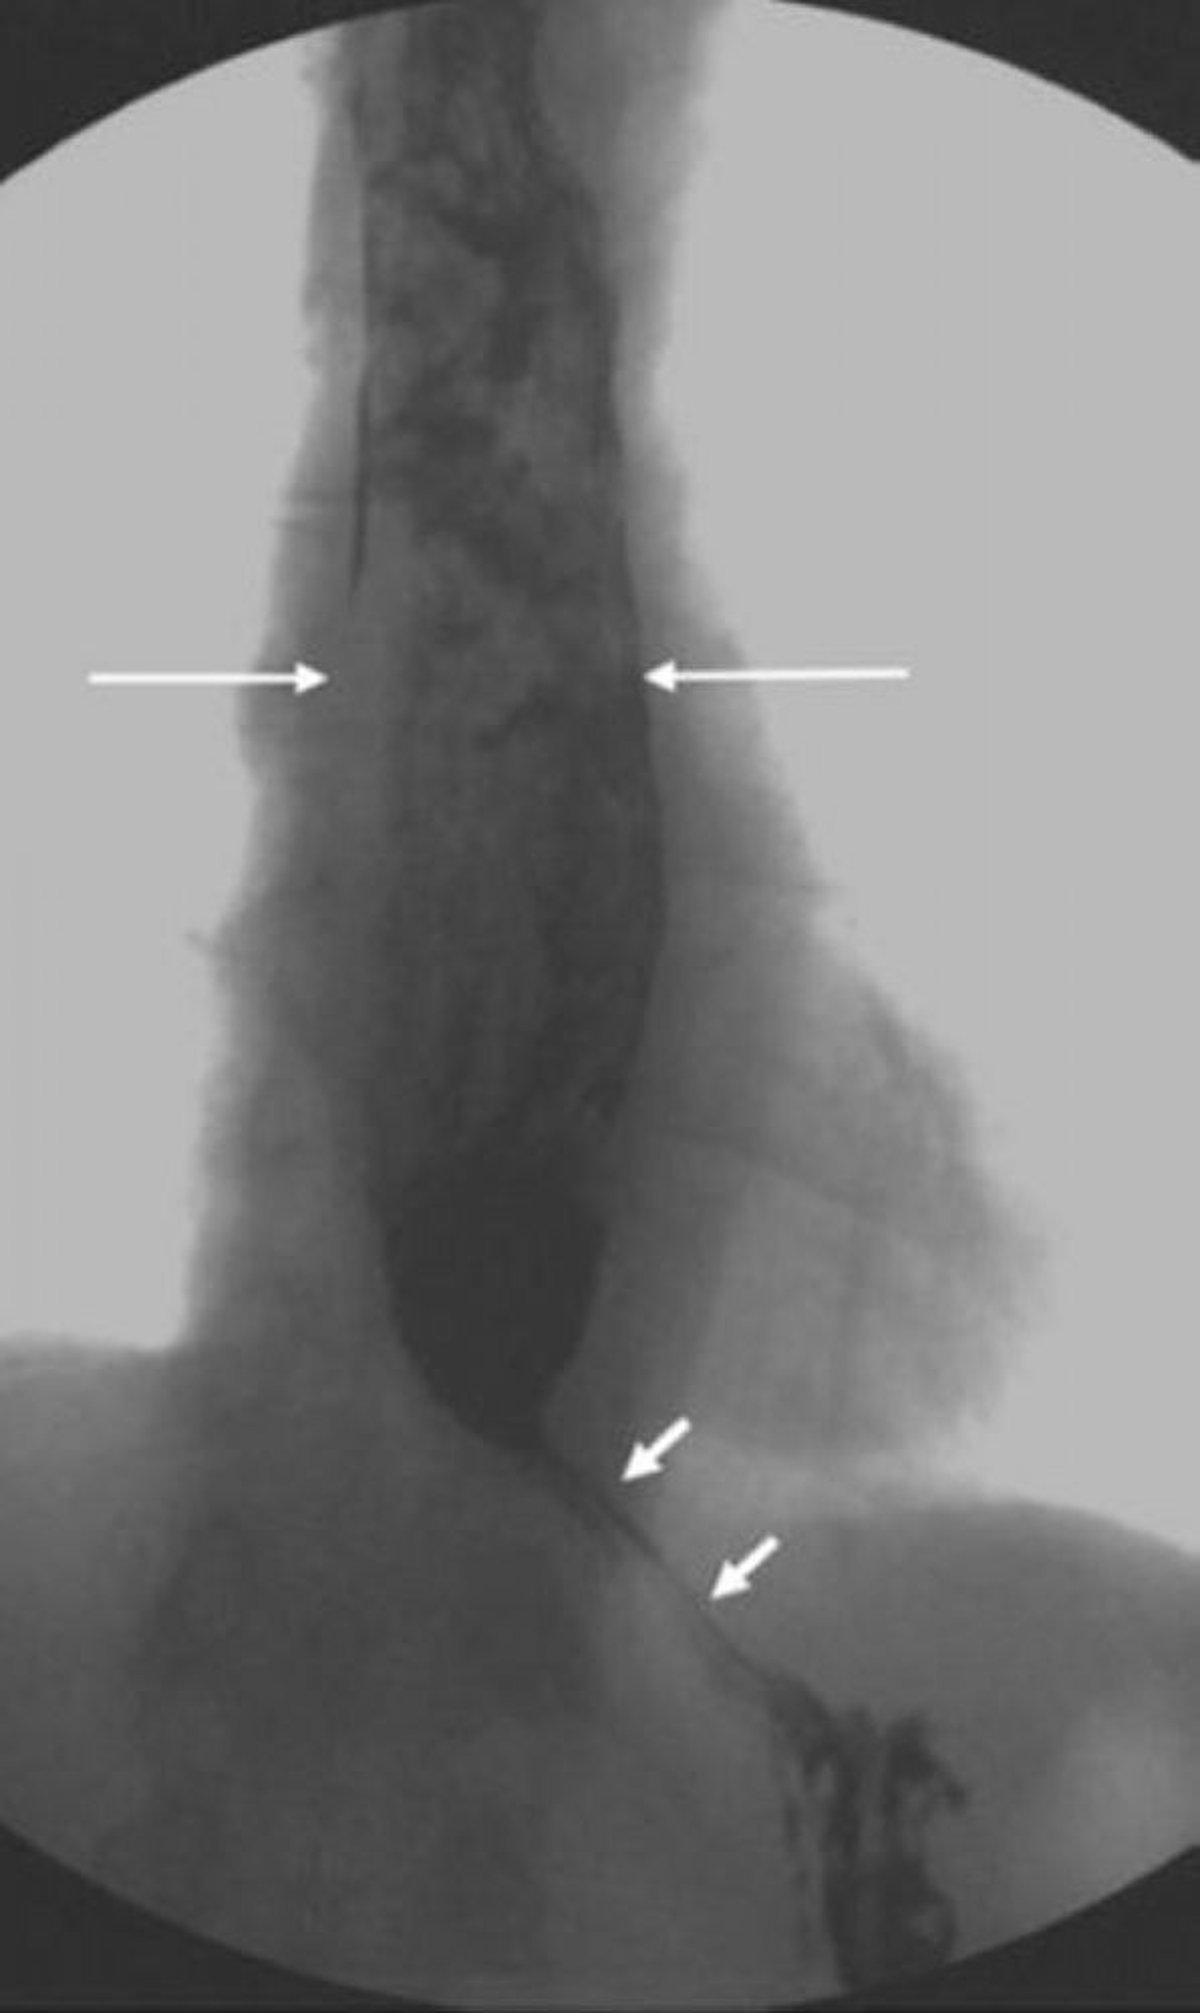

Transit baryté montrant un œsophage dilaté avec un aspect étroit en forme de bec au niveau du sphincter inférieur de l'œsophage

Cette image montre une achalasie avec dilatation proximale de l'œsophage et relaxation incomplète du sphincter inférieur de l'œsophage. Notez l'aspect inhomogène de la matière présente dans l'œsophage dilaté en raison de la nourriture non digérée qui n'est pas passée dans l'estomac (flèches longues). Dans l'achalasie sévère, seules de petites quantités de produit de contraste peuvent passer à travers une jonction œsophagogastrique en forme de bec (flèches courtes).